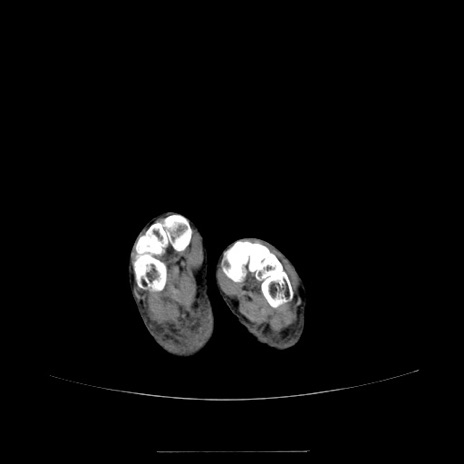

冠状断像